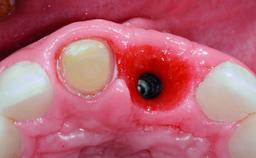

A 32-year-old female Caucasian patient with a compromised maxillary right central incisor was referred to us by a general dentist. Her chief complaints were discomfort and mobility of tooth 11 with unsatisfactory esthetics due to discoloration. The patient reported a previous trauma, some years earlier, as the origin of pathology on the afflicted tooth. Anamnesis was negative for any other dental or periodontal pathology in the remaining dentition. The patient did not take any medication and reported to be a light smoker (5–10 cigs/day). She had high esthetic expectations of her treatment. The extraoral examination revealed a high smile line with full exposure of her maxillary teeth and surrounding soft tissue in the area between the second premolars.

| Placement Protocol | Early or late implant placement |

| Bone Volume | Deficient horizontally, requiring prior grafting |